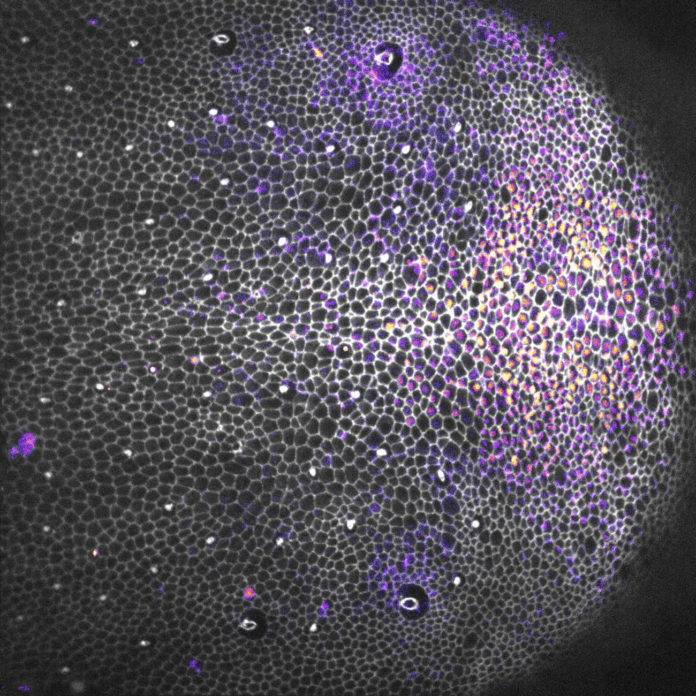

Dans certains tissus, notamment ceux qui se renouvellent vite, l’élimination des cellules mortes protège leurs voisines d’un sort similaire pour assurer la cohésion et l’imperméabilité de l’ensemble.

La mort cellulaire, garante de l’intégrité des tissus